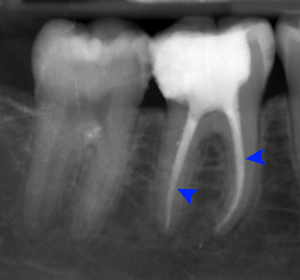

Illustration for the procedure for Root Canal Treatment When nerve or blood supply of the tooth is infected because of decay or an injury, root canal treatment is performed with the help of specialized instruments. Root canal treatment is done to save natural teeth. It is absolutely painless procedure and is performed under local anesthesia. At Sweet Smile, we provide faster solution by doing Root Canal Treatment in single day most of the times as it saves lot of time of patients and gives most predictable results. After Root Canal Treatment is completed, a full coverage crown is placed on that particular tooth so as to maintain & protect its function. Ar Sweet Smile we can achieve perfect Root Canal Treatment as we use most advance equipments like RVG - Digital X-Ray on Big Screen and Apex locator, which gives the accuracy of Root Canal Length up to 0.5 mm. |